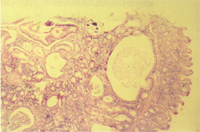

組織病變 : 公鼠小腸病變特別在迴腸粘膜增厚,絨毛增高、寬,腸腺上皮(Crypt epithelium )增生,腸腺管腔時呈囊狀擴張(Cystic dilatation),腔內並含有中性球呈隱窩炎( Cryptitis)。腸腺管增殖並向下方增生擴張,可穿透粘膜肌層(mucosal muscularis) 下方(圖 2)。此鼠的組織病變在盲腸較增厚,腸腺管上皮增生嚴重,濃染,分裂相( mitotic figures)很多,並在腸粘膜固有層(lamine proplia)與粘膜肌層浸潤有大量慢性炎症細胞呈肉芽腫性樣反應(granulomatous reaction)(圖3)。

雖然本病病原發生仍未十分瞭解,但一般飼養倉鼠,如長期飼養,慢毒性實驗時, 由其健康監測用到的哨兵鼠(sentinel animals)的例行解剖,有時可看到倉鼠小腸與結腸含有輕度腸炎,如colitis(圖4),感染有大量的鼠螺旋核原蟲(Spironucleus muris )組織病理為輕度腸絨毛頂尖部分之上皮細胞會壞死剝落,如取些腸內容物做塗抹片檢查,可發現有許多梨型狀原蟲,約7~8 × 2~5